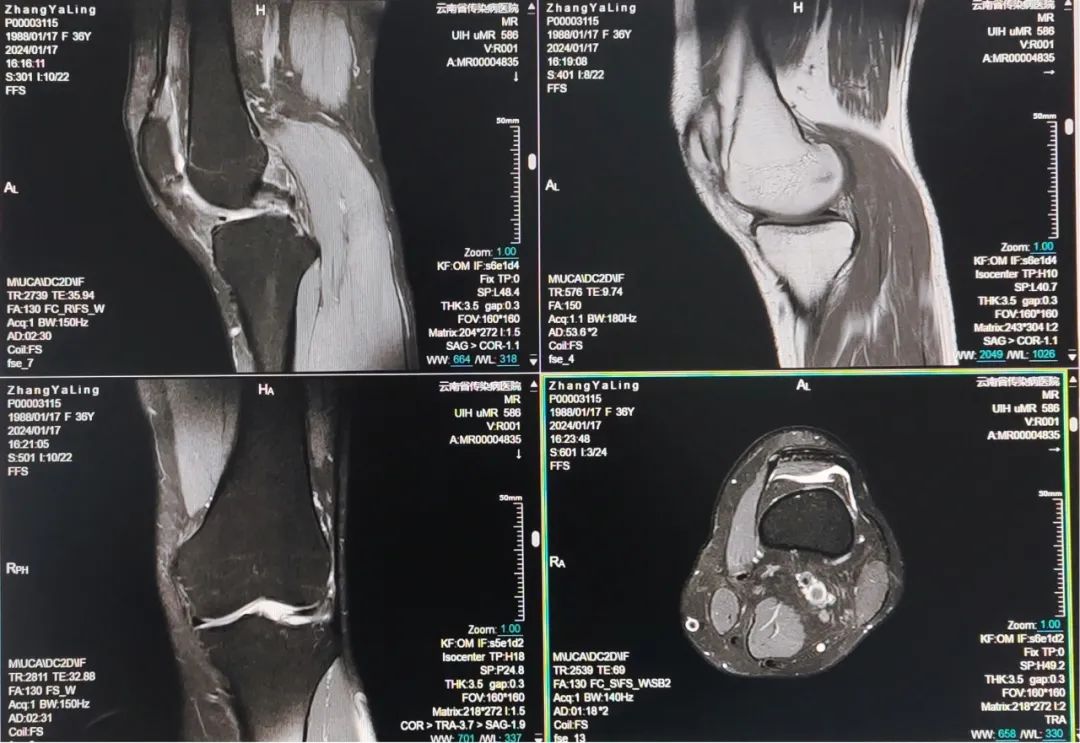

联影uMR586全数字超导磁共振成像系统搭载联影最新一代光梭成像技术,是目前国内外最先进的1.5T以下磁共振成像设备:在硬件方面,配置业内最先进的光梭成像平台,具有优异的磁场均匀性、高效的全数字化射频系统及一体化高密度相控阵线圈设计等顶级的硬件配置;在软件方面,量身定制如自由呼吸、GRE、ARMS等运动伪影抑制技术,体部磁敏感技术等多种高级应用软件,在为患者带来更高舒适度的同时,有效提高扫描速度、显著提高图像质量、提高检查成功率和微小病灶检出率。

uMR 586光梭磁共振成像系统具备极高分辨力,能够清晰显示颅脑、脊柱、腹部、血管、软骨韧带等部位,对软组织损伤、骨关节损伤、椎间盘突出、脊髓疾病等诊断优于X线及CT扫描,检查更为精准且无辐射,为早期发现、早期诊断、早期治疗疾病提供有力的技术保障。

6. 骨与关节:骨内感染、肿瘤、外伤的诊断与病变范围,尤其对一些细微的改变如骨挫伤等有较大价值,关节内软骨、韧带、半月板、滑膜、滑液囊等病变及骨髓病变有较高诊断价值;